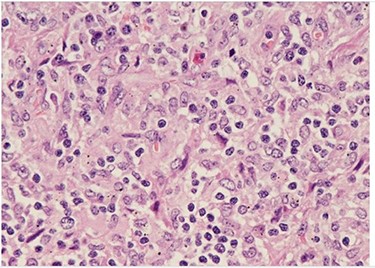

H&E slide (medium magnification, 20×) shows activated lymphocytes, immunoblasts and plasmacytoid monocytes.

H&E (High power magnification, 40×) shows characteristic large activated lymphoid cells, karyorrhectic debris and histiocytes. The histiocytes are enlarged with crescentic nuclei and phagocytized nuclear debris. Neutrophils are absent.